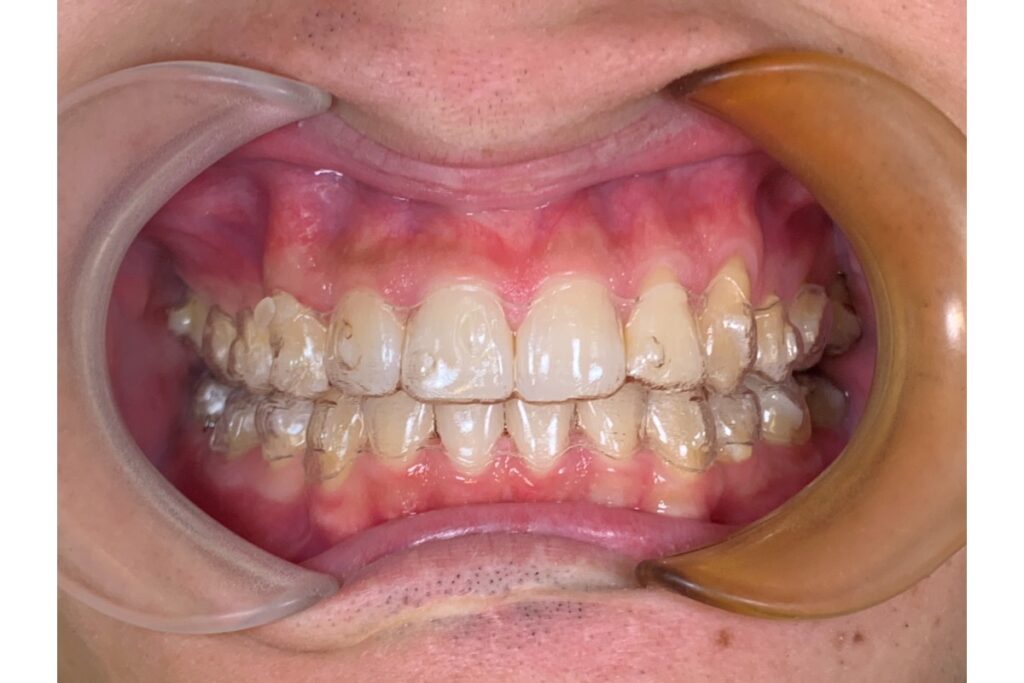

装置代・調整代・検査代・補助手段代などを含めた総額見積もりを確認。 - 男性患者対応の実績や症例を見る

男性患者の症例写真・口コミ・対応実績がある医院を選ぶ。